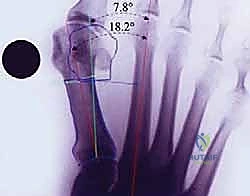

- الأشعة السينية (X-Rays) أثناء تحمل الوزن: هذا هو الفحص الذهبي. يجب أن تُؤخذ صور الأشعة والمريض واقف (يتحمل وزنه على قدميه). من خلال هذه الأشعة، يقوم الدكتور هطيف بقياس الزوايا الهامة بدقة هندسية:

- زاوية إبهام القدم الأروح (HVA): الزاوية بين المشط الأول والسلامية القريبة.

- الزاوية بين الأمشاط (IMA): الزاوية بين المشط الأول والمشط الثاني.

يصبح هذا التشوه حالة مَرَضية تستدعي الانتباه الطبي عندما يبدأ المريض في المعاناة من آلام موضعية، وعندما تزيد زاوية انحراف إصبع القدم الكبير (المعروفة طبياً باسم زاوية HVA - Hallux Valgus Angle) عن 15 درجة مئوية. هذه الزاوية هي المقياس الشعاعي الدقيق لمدى انحراف إصبع القدم الكبير عن المحور الطولي الطبيعي للقدم. وكلما زادت هذه الزاوية، زادت شدة التشوه والأعراض المرافقة له.